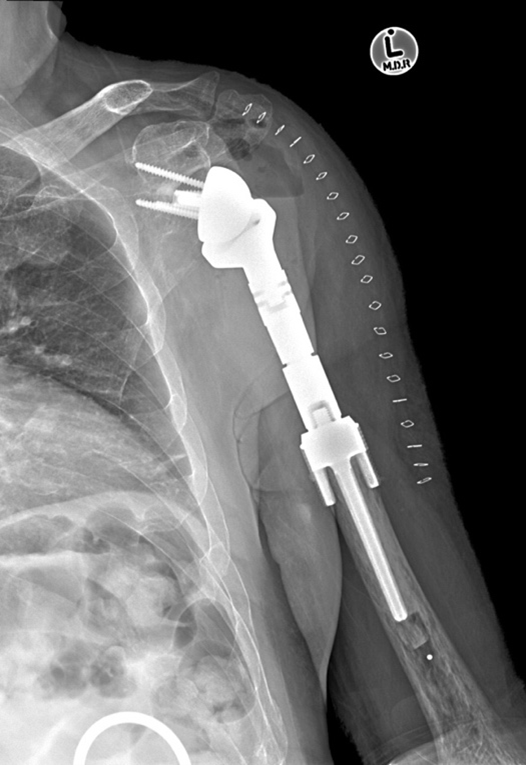

- More than 90% of cases are amenable to limb salvage which involves the resection of the tumour with a cuff of normal tissue to minimise the risk of local recurrence and reconstruction of the limb.

- There are many ways to do this but one of the more popular methods is with an endoprosthesis which is inserted into the space left by the tumour to give structure to the limb and allow function. An example is given below.